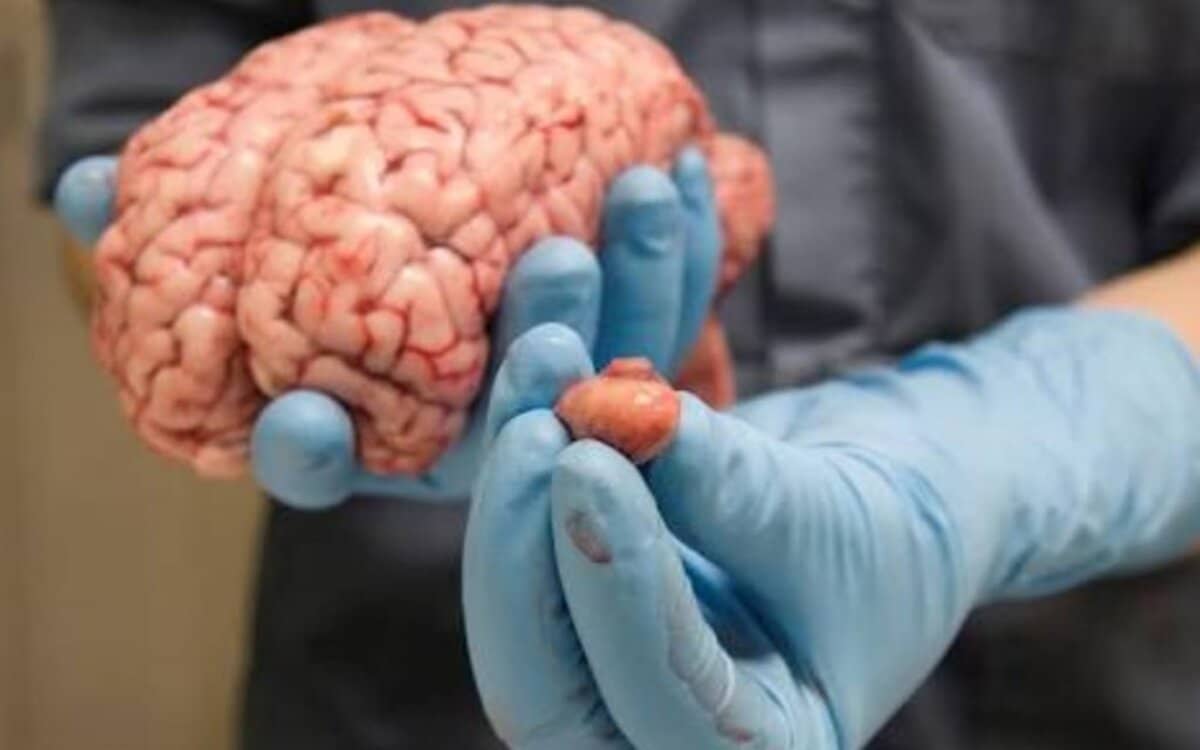

يتعرض الكثير من الأشخاص إلى الإصابة بالأورام التي تستهدف الغدة النخامية، وفي الغالب تكون هي أورام حميدة، وغير خبيثة، تستهدف تلك الغدة، التي تقع في منطقة قاعدة الدماغ، ويكون مكانها خلف الأنف مباشرة، ولا يزيد حجمها عن حجم حبة البازلاء، وتحت عنوان تجربتي مع ورم الغدة النخامية، خاض الكثيرون تجارب واتبعوا طرق لعلاج الغدة والأورام بداية من من استعمال العقاقير والأدوية، التي تستطيع التحكم في نمو الورم وتطوره، وآخرون خاضوا عملية استئصال الورم ذاته.

في البداية يجب التعريف بورم الغدة النخامية، بأنه عبارة عن خلايا تنطور بشكل وطريقة شاذة في الغدة النخامية، وتعمل عدد من أورام الغدة النخامية إلى إفراز الهرمونات بإفراط، وخاصة تلك التي تنظم مهام جسد الإنسان الضرورية، كما ينتج عن بعض أورام الغدة النخامية مستويات أضعف من هرمونات الغدة النخامية.